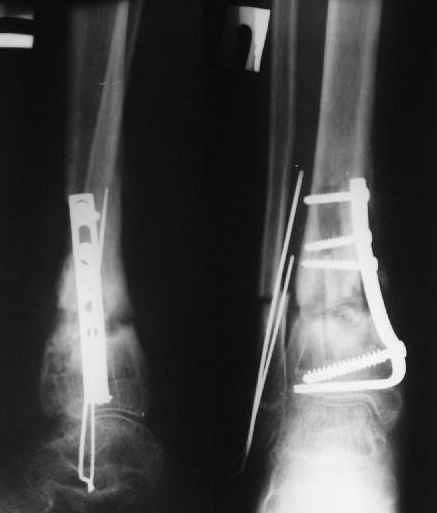

В январе 2005: варусная деформация н\3 голени, болевой с-м, комбинированная контрактура г\стопного сустава, нейропатия м\берцового нерва сохраняется слабость разгибания 1 пальца.

Операции: 1 Клиновидная резекция на вершине деформации м\берцовой кости.

2 Тугоподвижный ложный сустав н\3 б\берцовой кости. Рубцы выполняющие пространство между отломками, канал проксимального отломка иссечены.

Одномоментное устранение деформации, остеосинтез Г-образной пластиной.

Пластика по Хахутову.

Заживление проксимальной части раны вторичным натяжением без нагноения. Рана зажила. Спицы удалены через 1,5 недели после операции.

Особого смысла в них не было.

Учитывая фон (интеллект, etc) гипсовая повязка.

A> В январе 2005: варусная деформация н\3 голени,

А на вытяжении и в гипсповязке в течение 4 мес варуса видно не было?

Чего было ждать?

A> Операции: 1 Клиновидная резекция на вершине деформации м\берцовой кости.

A> 2 Тугоподвижный ложный сустав н\3 б\берцовой кости.

Т.е. на фоне некоторого наверняка имевшегося укорочения голени

произвели ее дополнительное укорочение?

Или как?

A> Спицы удалены через 1,5 недели после операции.

A> Особого смысла в них не было.

Фиксация